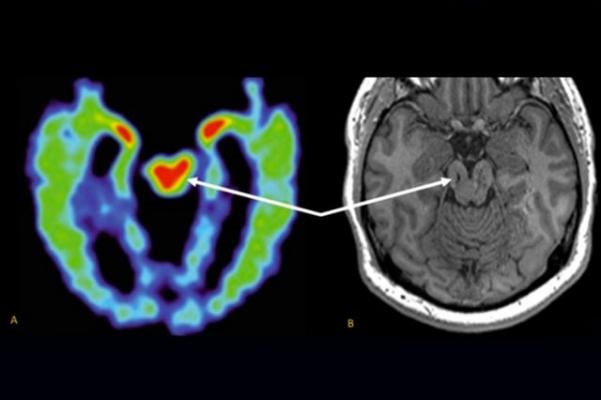

An Mri Contrast Enhanced T1 Weighted Image Showing Interval Resolution Download Scientific Diagram